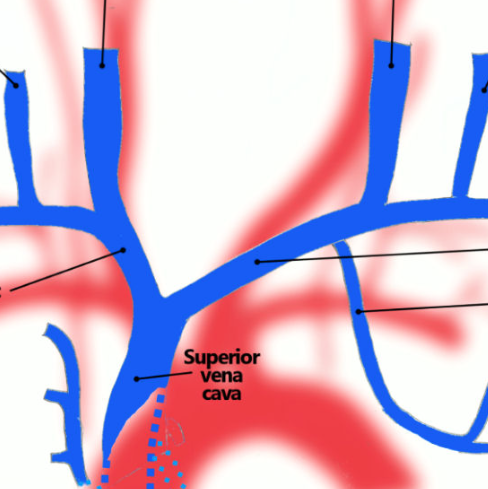

Describe the anatomy of the arterial great vessels

DEscribe the anatomy of the neck great veins